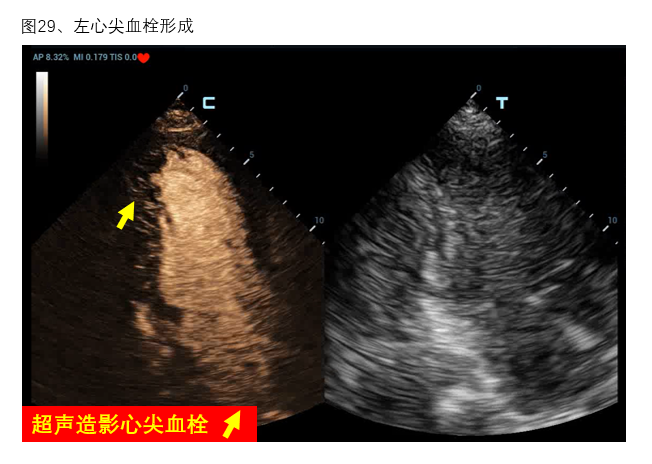

五、特殊超声检查和技术

1、超声造影 超声造影常用于创伤出血患者的脏器破裂、出血部位查找,也常用于心腔内膜的清晰显示。虽然目前在ECMO患者中使用超声造影剂的安全性没有足够证据支持,但已有少量病例报道应用超声造影协助发生南北综合征的VA-ECMO患者寻找血流接触平面位置、判断主动脉瓣反流、协助明确左心室血栓形成(图29)及撤机后使用超声造影协助评估穿刺点部位血管并发症等多方面应用[25-28]。

图29